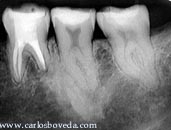

Segundo

y Primer Molar Superior Derecho

Primer

Molar Superior Derecho